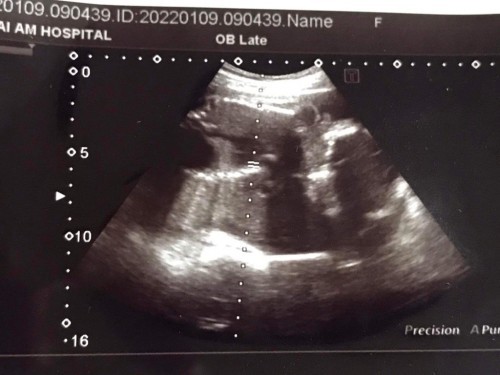

เพศ

ยังงี้มองออกไหมคะ ว่าเพศอะไร

ฝากด้วยค่ะ อันนี้หญิงรึชายค่ะ

ชายใหมคะแม่ เหมือนรุปไข่น้อง

ชัดเลยคะแม่ น้องเป็นผู้ชายคะ

ฝากดูด้วยค่ะว่านี้ญ.หรือช.

น่าจะผช.นะคะ ไข่กลมเชียว😁😁😁

ชายค่ะ ทั้งพวงทั้งจู๋ ชัดมาก

เหมือนผู้ชายเลย เดาเอานะค่ะ

ผู้ชายค่ะ เห็นทั้งพวงเรย 😂😂